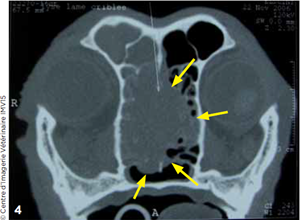

Photo 1 Masse tissulaire (flèche bleue) observée dans le cornet nasal droit (flèche jaune) lors de la rhinoscopie.

La rhinoscopie montre, dans le cornet nasal droit, une volumineuse masse à contours irréguliers, hyperhémiée (Photo1). Sa manipulation provoque des saignements. Des biopsies sont réalisées.